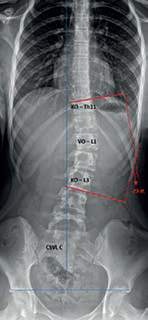

Obr. 1 Thorakolumbální skolióza Lenke typ 5 (Th11 – 23 sin. – L3), CSVL C – křivka tedy vykazuje abnormalitu ve frontální rovnováze. KO = koncový obratel; VO = vrcholový obratel. Horizontální linie procházející stříškami pánevních acetabul vylučuje asymetrii výšek kyčelních kloubů. Zdroj: Ortopedická klinika FZS UJEP a MN UL.Jedná se o jeden z aktuálně používaných klasifikačních systémů, díky němuž lze popsat až 42 typů křivek. Lenke rozlišuje šest základních typů deformit, které jsou děleny dle lokalizace a jednotlivých typů patologických křivek páteře. V rámci tohoto systému může být dále hodnocen tzv. lumbar modifier A–C dle průběhu tzv. centrální sakrální vertikální linie (CSVL), případně tzv. thoracic sagittal modifier, kdy je na sagitálních snímcích determinována eventuální hyper‑/hypokyfóza.11 Základní hodnocení skoliotické křivky popisuje obrázek 1.

• Cobbův úhel – hlavní parametr skoliotické křivky. Při jeho konstrukci nejprve určíme koncové obratle, které ohraničují skoliotickou křivku kraniálně a kaudálně. Následně zakreslíme tečny jejich odlehlých krycích lišt (tedy horní lišta u kraniálního obratle a dolní lišta u kaudálního obratle), z těchto tečen poté sestrojíme kolmice. Doplňkový úhel v oblasti jejich průsečíku je úhlem Cobbovým. Sestrojení Cobbova úhlu je popsáno na obrázku 1.